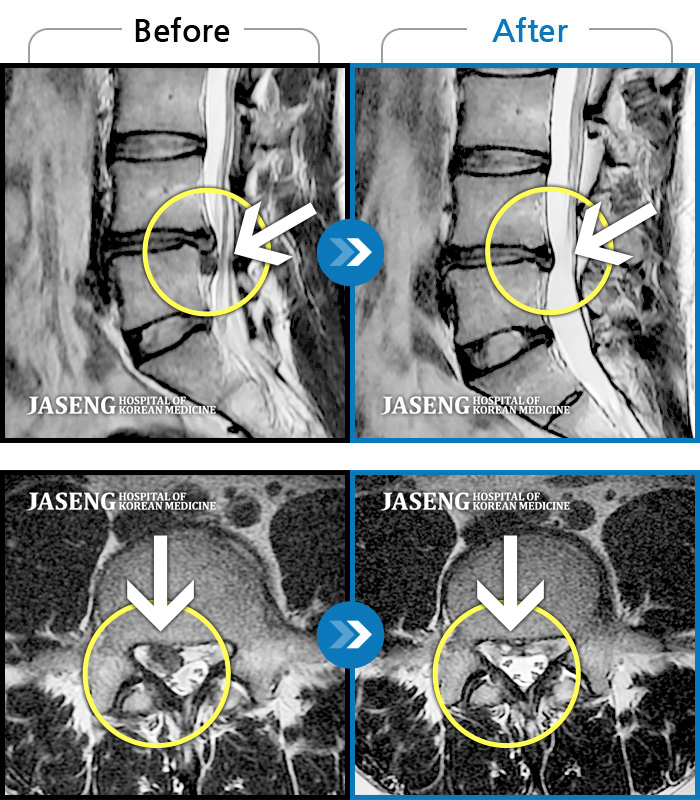

Before

After

환자에게 사전 동의를 받아 동일 조건에서 촬영되었습니다.

개인에 따라 치료 후 부작용이 발생할 수 있으니 의료진과 상담 후 치료를 진행하시기 바랍니다.

허리와 좌측 다리가 당겨 보행이 불가능했다.